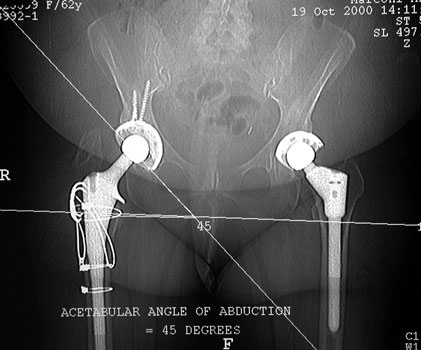

Acetabular component lateral inclination

• Transischial line obtained on pilot image

• Line drawn through cup

CT Measurements

Cup Anteversion

• Transischial line obtained on axial image through ischial tuberosities (A)

• Transischial line transposed to an axial image of the cup (B)

• A second line is drawn through the anterior and posterior lips of the cup

• Anteversion angle is formed intersection of transischial line and line through cup